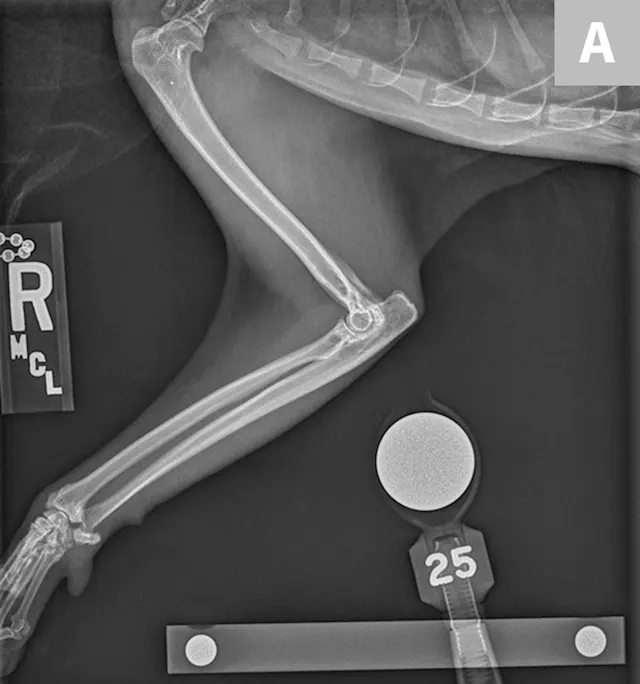

FIGURE 3

Lateral (A) and dorsoventral (B) views of the pelvis. Figure A shows a moderate amount of the smoothly marginated, bridging, bony proliferations surrounding the 2nd through 5th coccygeal vertebrae. A moderate amount of kyphosis is present on the tail, centered in the bony proliferation. A mild amount of irregularly marginated bony proliferation is present surrounding the facet joint of the C5-C6 intervertebral disk space. Figure B shows poor coverage of the right femoral head by the acetabulum. A moderate amount of irregularly marginated bony proliferation is present on the cranial and caudal aspects of the acetabulum and femoral neck. There is decreased soft tissue associated with the left pelvic limb as compared with the right. A small osteophyte on the left cranial acetabulum can be noted. Image courtesy of Dr. Karen Perry. Interpretation: Chronic, healed caudal vertebral fracture, C2-C4. Moderate, right coxofemoral osteoarthritis and mild left coxofemoral osteoarthritis